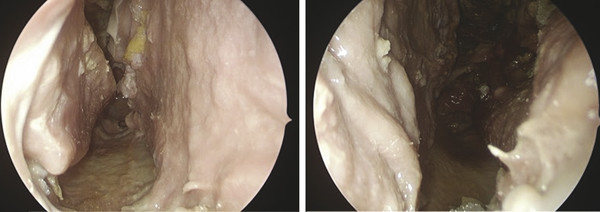

It would be advisable to place nasal packing during 48 to 72 hours, as well as silicone nasal splints anchored in the most anterior region of the remains of the nasal septum.